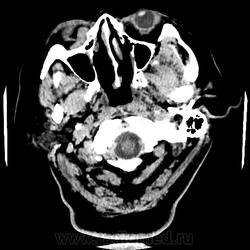

Женщина 48 лет, поступила с подозрением не ОНМК. На КТ -данных за ОНМК не обнаружено, но в правой орбите ретробульбарно мягкотканное образование +45HU, признаков деструкции и ремоделирования костных структур орбиты не наблюдается, медиальная и нижняя прямая мышца отчетливо не дифференцируются, зрительный нерв тесно прилежит к данному образованию. После КУ гомогенное накопление КВ и повышение плотности до +65HU. Экзофтальм. Жалобы на снижение зрения. Год назад делала МРТ ГМ, на снимке патологии орбит не увидел. Идиопатическая псевдоопухоль орбиты?

В мягких тканях носогубного треугольника справа тоже образование.

Натив